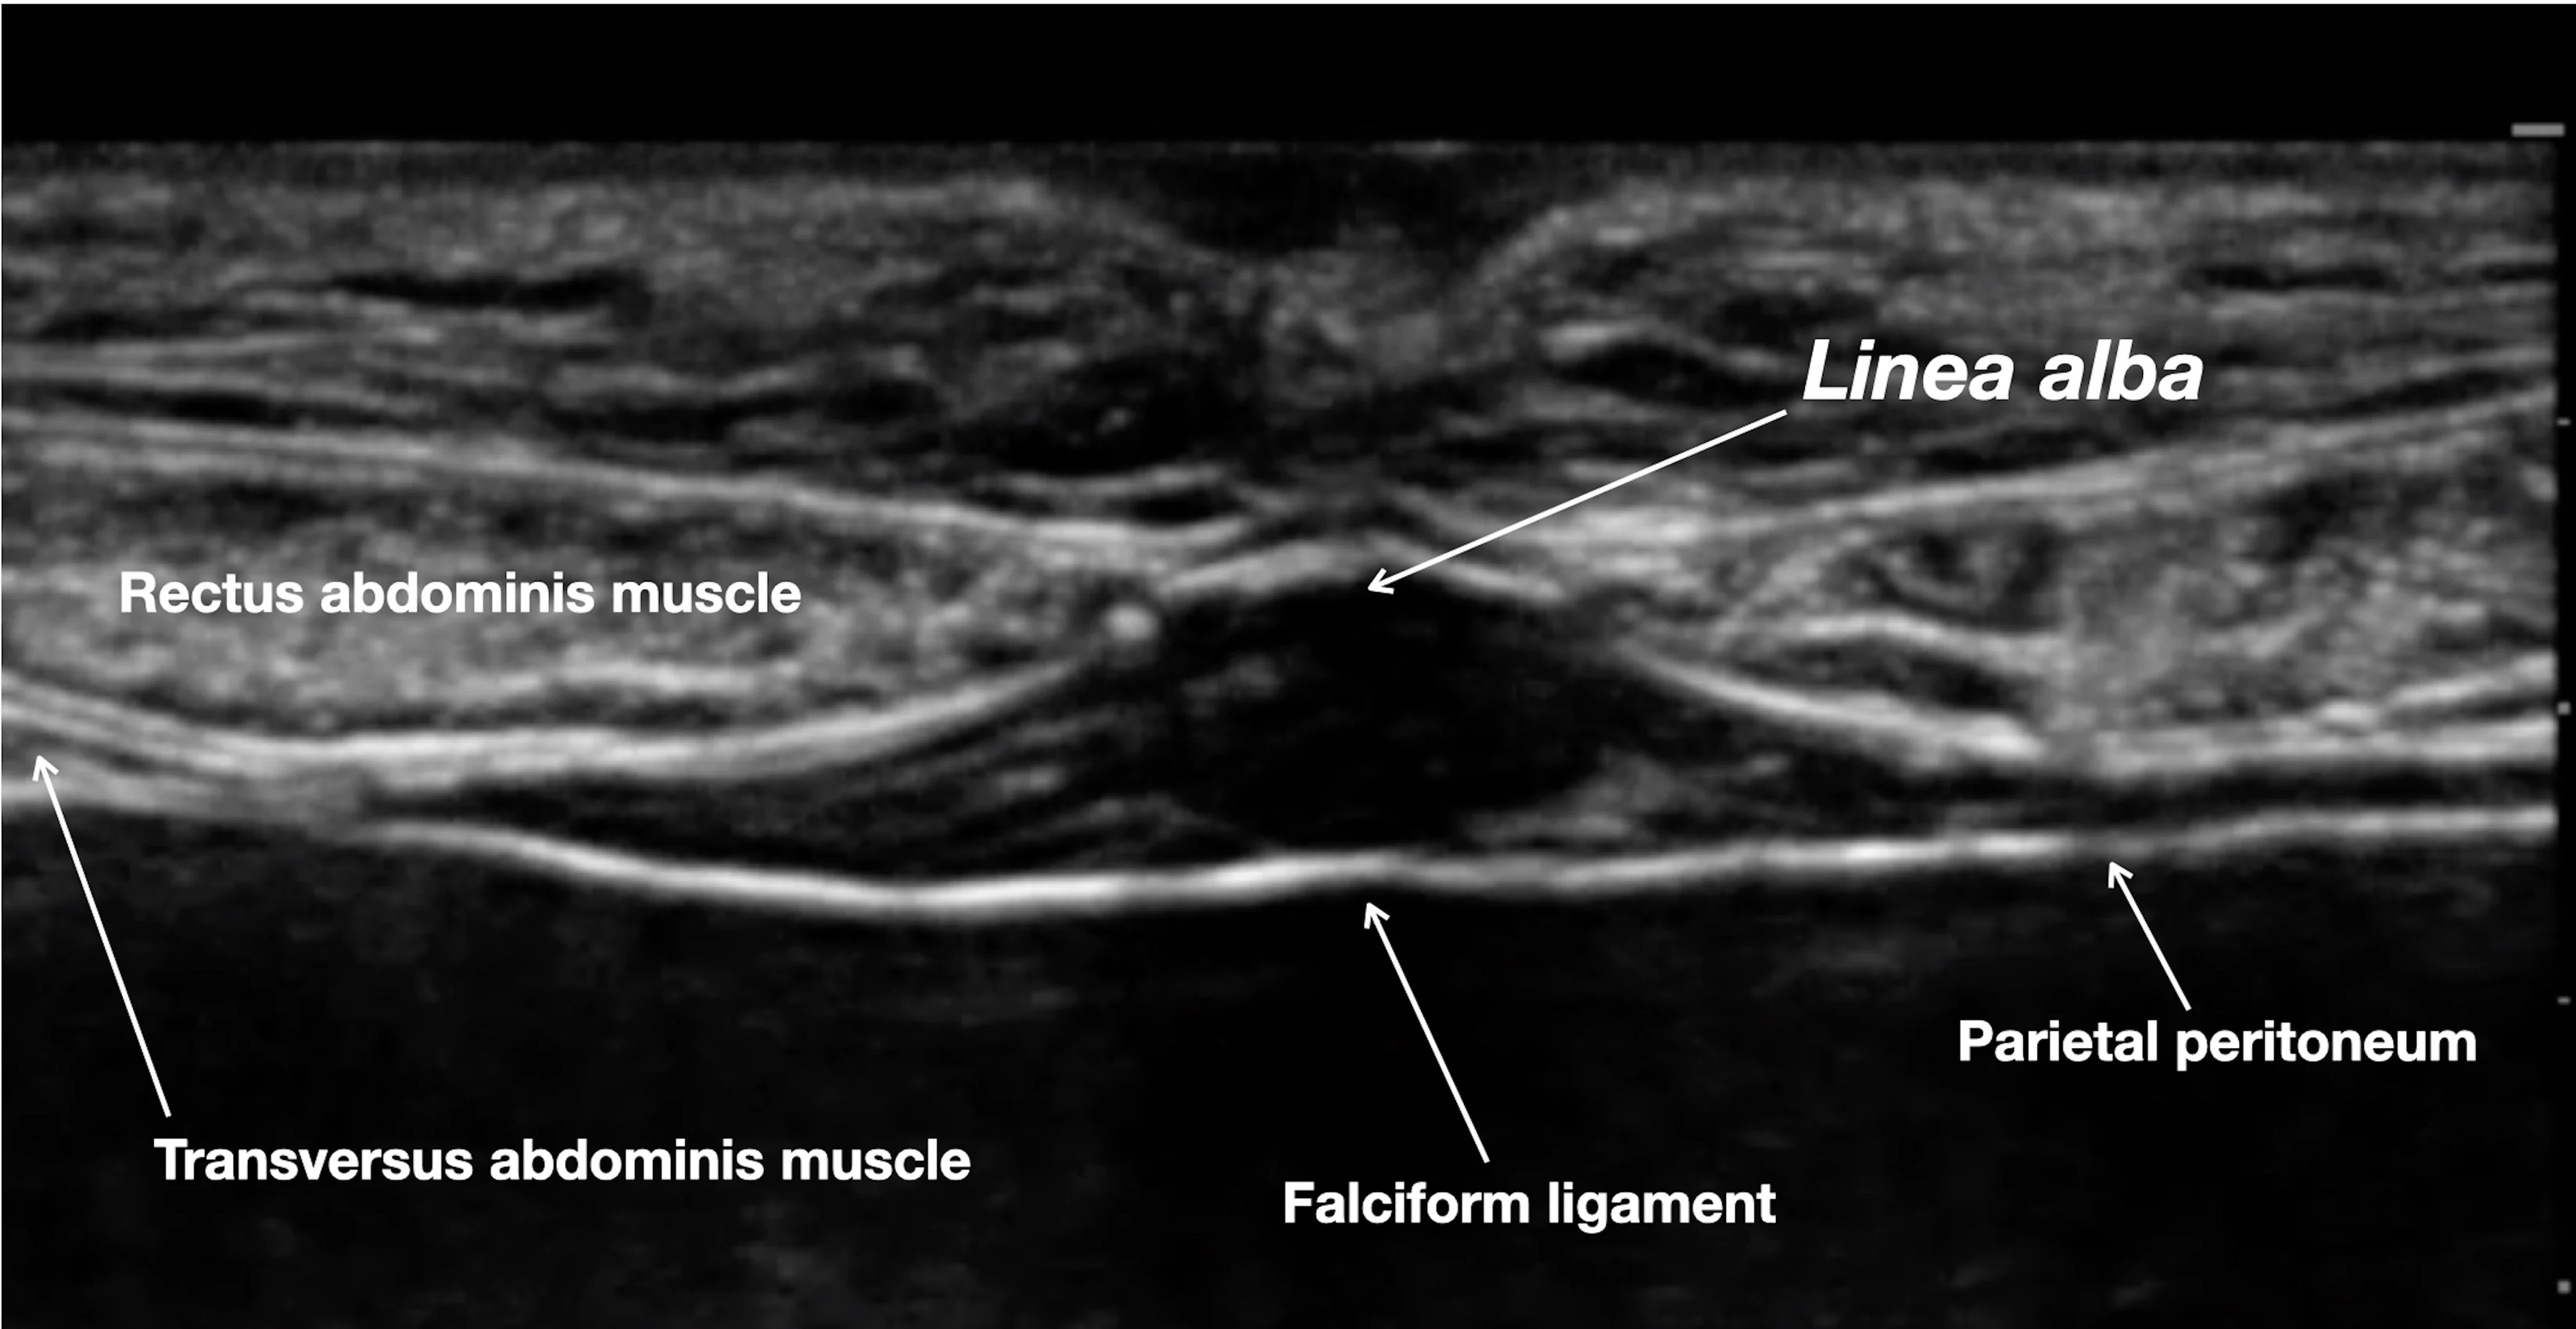

Step 6: Visualize the Abdominal Wall via Ultrasound

Position the ultrasound transducer on the cranial abdomen over the midline. Adjust the ultrasound depth and gain to obtain a clear image of the abdominal wall.

Author Insight

The linea alba, falciform ligament, parietal peritoneum, and rectus abdominis muscle should be visible.